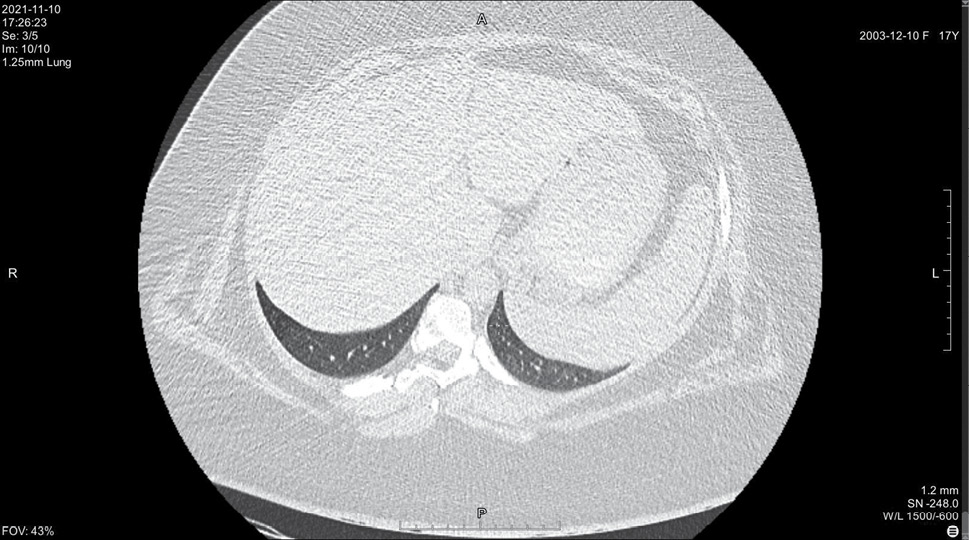

На 14 день болезни (10.11, 7 день госпитализации) была выполнена спиральная компьютерная томография грудной клетки, где выявлены признаки двусторонней интерстициальной полисегментарной пневмонии (рис. 1–8). Форма грудной клетки описана как обычная. Легочные поля расправлены. На томограммах бронхиальное дерево визуализировано до субсегментов: сами бронхи не деформированы, их просвет в пределах нормы, устья свободны, проходимость сохранена на всем протяжении. Во всех сегментах с обоих сторон определялись полиморфные, сливные участки уплотнения легочной ткани по типу матового стекла с участками консолидации. На этом фоне были видны просветы бронхов. Определялись фиброзные тяжи в проекции апикальной плевры обоих легких. Контуры диафрагмы четкие, синусы свободные, свободная жидкость в плевральной полости отсутствовала. Трахея обычной формы и размеров, карина острая. Сосудистые структуры верхнего средостения с четкими контурами и нормального диаметра, стенки сосудов без кальцинатов. Медиастинальные лимфоузлы и лимфоузлы корней обоих легких (без контрастного усиления) визуализированы единично, не увеличены. Сердце расположено обычно, размеры в пределах нормы. Выявлены умеренные дегенеративно-дистрофические изменения грудного отдела позвоночника. Мягкие ткани грудной клетки без особенностей. По заключению врача-рентгенолога, объем пораженной легочной паренхимы достигал 95%. Наиболее вероятно, что патологический процесс у пациентки имел вирусную природу.

Рисунок 7. Томограмма легких на уровне ThIX

Рисунок 8. Томограмма легких на уровне ThX